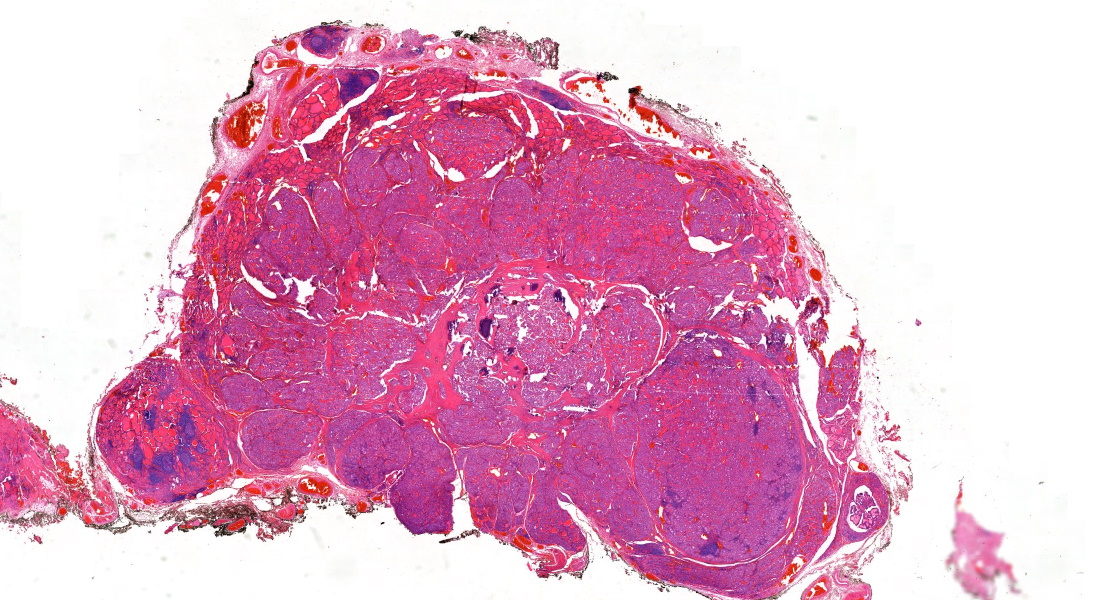

Mark Ong

Mark Ong@DrMarkOng·

60+ female. Inguinal lymph node core biopsy. If you had to choose one diagnosis on H&E alone, what would you go for? #hemepath #pathology

Mark Ong tweet media